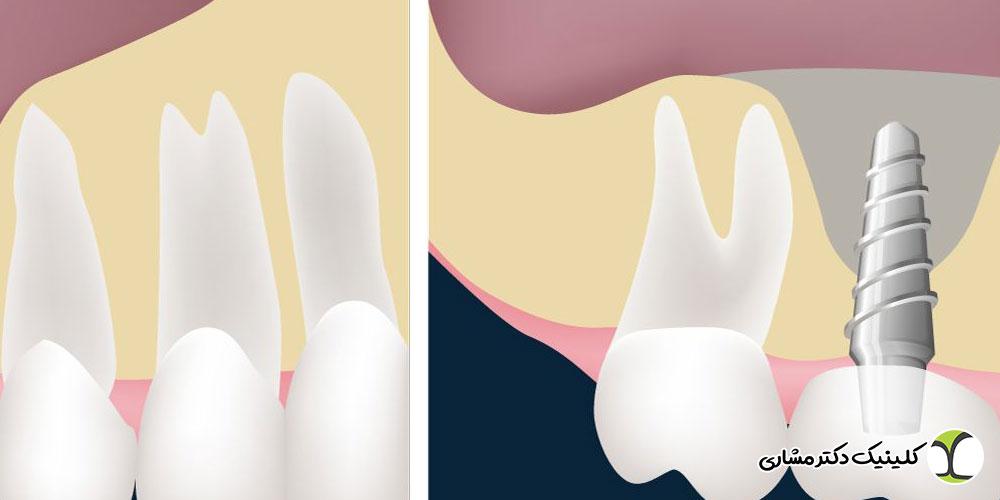

پیوند استخوان یک جراحی تخصصی برای تقویت بافت استخوانی فک است که قبل از کاشت ایمپلنت انجام میشود. زمانی که استخوان دندان به دلیل عوامل مختلف ضعیف، تحلیلرفته یا ناکافی باشد، پزشک با استفاده از مواد استخوانی طبیعی یا مصنوعی، حجم و تراکم فک را افزایش میدهد. داشتن استخوان سالم و محکم برای موفقیت ایمپلنت ضروری است، زیرا پایداری ایمپلنت به مقاومت استخوان اطراف آن وابسته است. پیوند استخوان معمولاً در موارد زیر توصیه میشود:

سینوس لیفت چیست؟

سینوس لیفت نوعی جراحی بازسازی استخوان است که فقط در فک بالا و در ناحیهای که سینوسهای فکی قرار دارند انجام میشود. وقتی استخوان فک بالا به دلیل تحلیل یا نزدیکی بیش از حد به سینوس حجم کافی برای کاشت ایمپلنت ندارد، جراح با بالا بردن غشای سینوس و افزودن استخوان، فضای مناسب ایجاد میکند.

تفاوت بین سینوس لیفت و پیوند استخوان

اگرچه هر دو روش با هدف افزایش حجم استخوان انجام میشوند، اما کاملاً یکسان نیستند.

| محل انجام | فک بالا یا پایین | فقط فک بالا (نزدیک سینوس) |

| هدف اصلی | تقویت استخوان تحلیلرفته | افزایش ارتفاع استخوان زیر سینوس |

| میزان پیچیدگی | معمولاً سادهتر | پیچیدهتر و تخصصیتر |

| زمان بهبودی | کوتاهتر | طولانیتر |

| علت استفاده | تحلیل استخوان یا کمبود تراکم | نزدیکی زیاد سینوس به محل ایمپلنت |